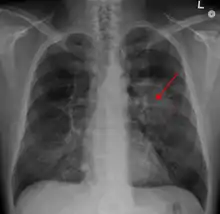

| A chest X-ray showing a tumor in the lung (marked by arrow) | |

A person suspected of having lung cancer will have imaging tests done to evaluate the presence, extent, and location of tumors. First, many primary care providers perform a chest X-ray to look for a mass inside the lung.[8] The X-ray may reveal an obvious mass, the widening of the mediastinum (suggestive of spread to lymph nodes there), atelectasis (lung collapse), consolidation (pneumonia), or pleural effusion;[9] however, some lung tumors are not visible by X-ray.[5] Next, many undergo computed tomography (CT) scanning, which can reveal the sizes and locations of tumors.[8][10]